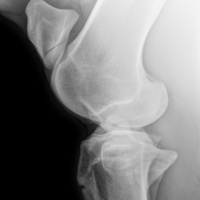

Cuattro DR HD è l'ultimo sistema radiografico digitale ad alta definizione per piccoli animali ed equini prodotto dal fornitore leader di soluzioni radiografiche digitali veterinarie.

Innovativo, veloce, efficace, sicuro e ancora più brillante: l'ultimo sistema a raggi X, Cuattro DR HD soddisfa i più alti standard nella diagnostica radiografica veterinaria.

• Visualizza i dettagli come mai fino ad ora : 17x17'’ 100 microns High definition detectors combinati con la migliore tecnologia post-elaborazione nel nostro software per immagini di altissima qualità